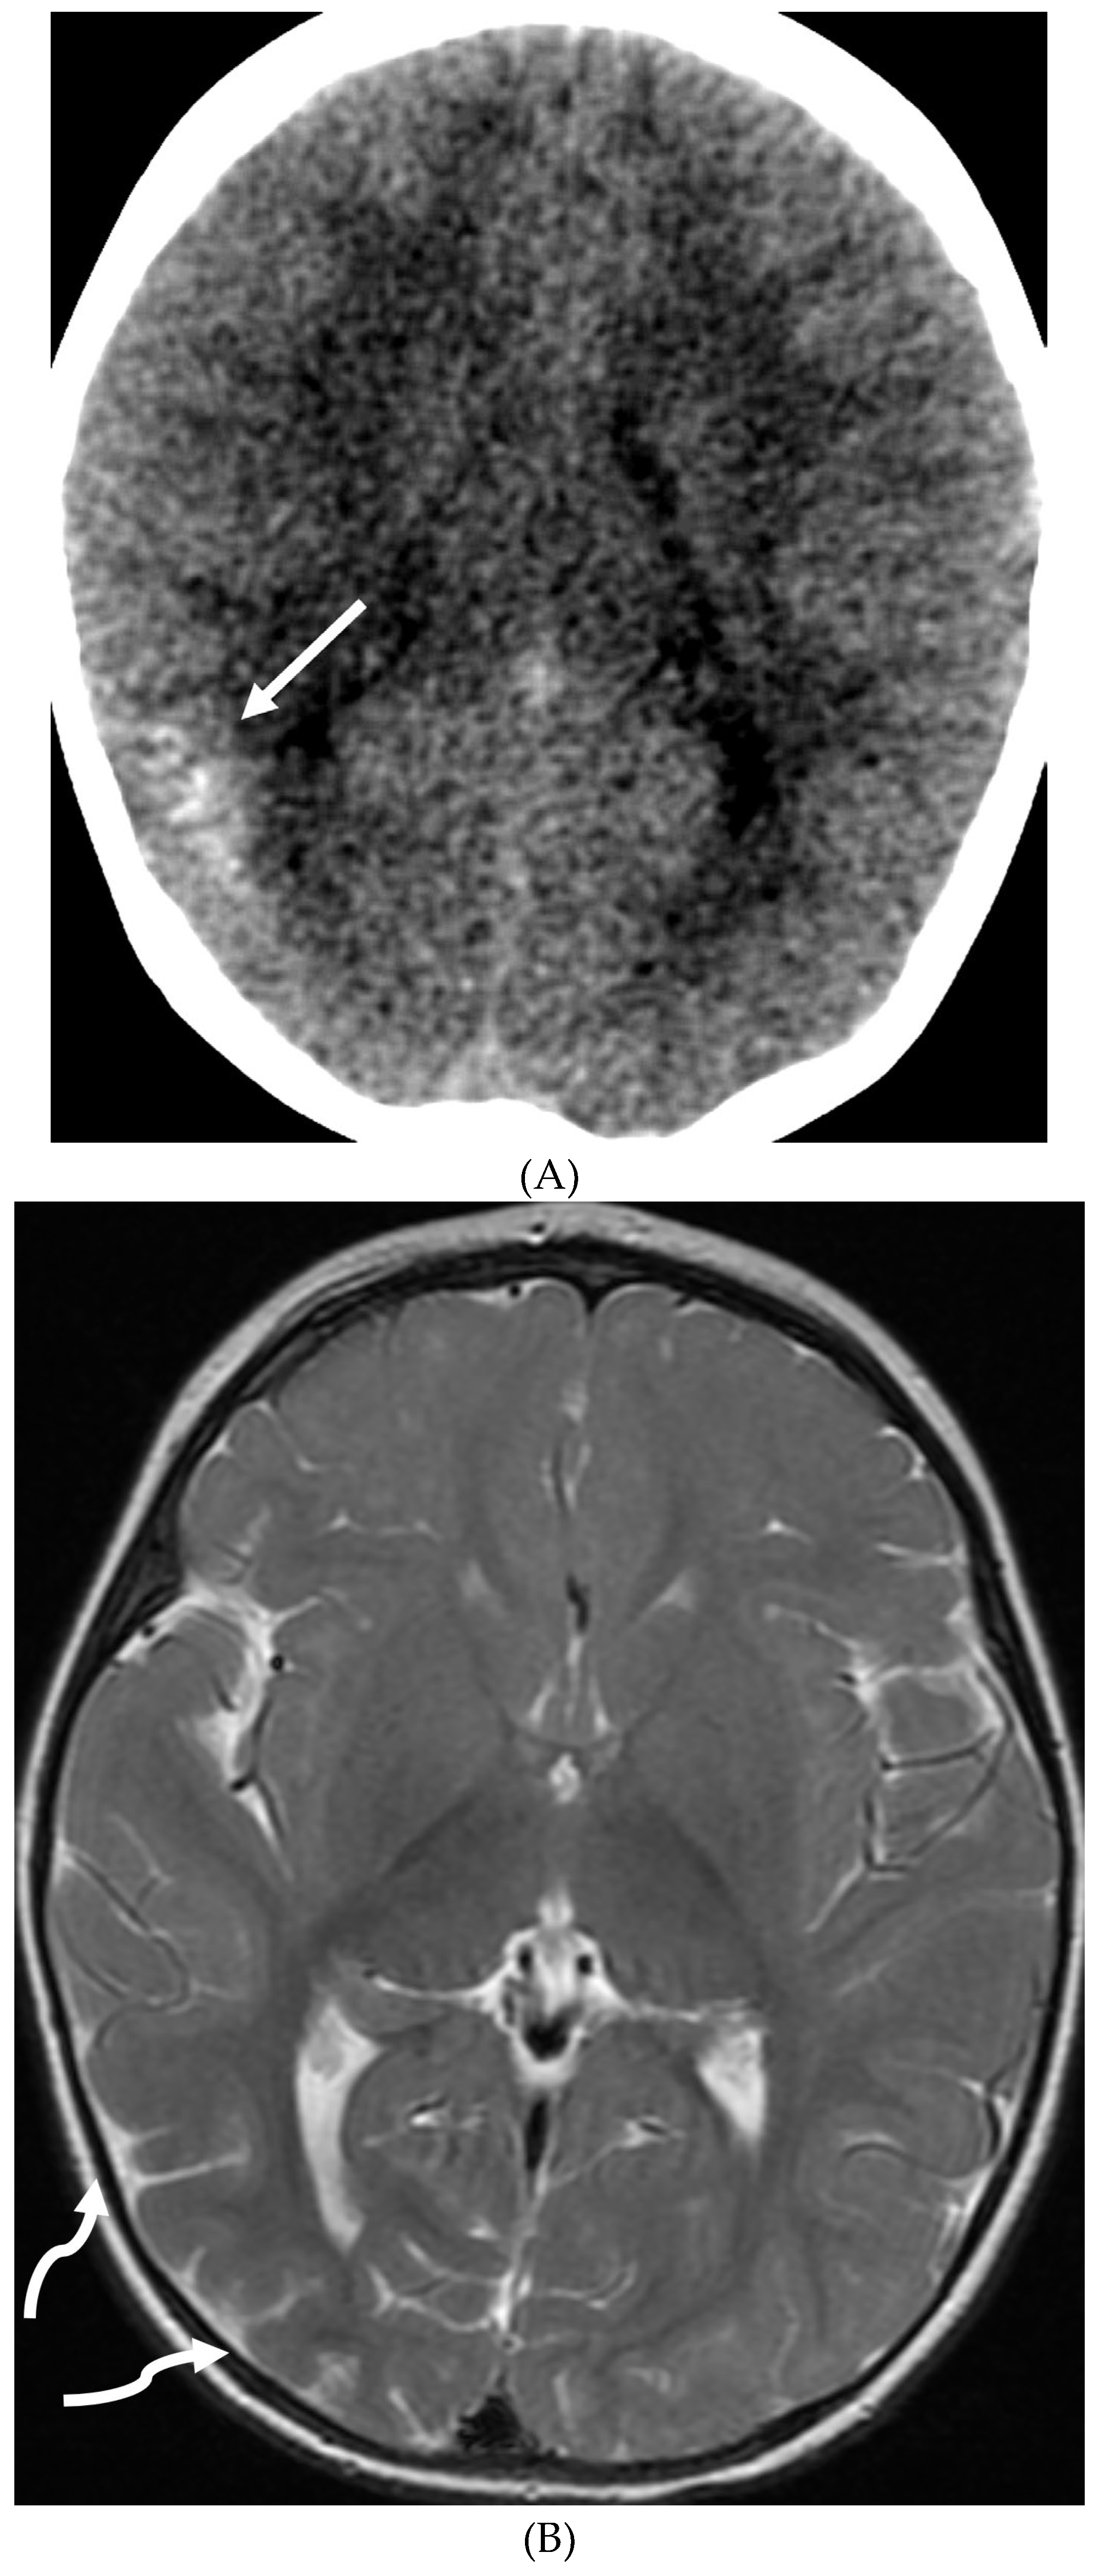

SYSTEMIC MENINGEAL METASTASES (SMM)

- Kralik SF, O'Neill DP, Kamer AP, Rodriguez E, Ho CY. Radiological diagnosis of drop metastases from paediatric brain tumours using combination of 2D and 3D MRI sequences. Clin Radiol. 2017 Oct;72(10):902.e13-902.e19. Epub 2017 May 22. PMID: 28545686. [CrossRef]

- Silva, F.A.B., Senerchia, A.A., Cappellano, A. et al. Medulloblastoma and Drop Metastasis: MRI Evaluation and Optimized Protocol. Curr Radiol Rep 3, 26 (2015). [CrossRef]

- Harrison SK, Ditchfield MR, Waters K. Correlation of MRI and CSF cytology in the diagnosis of medulloblastoma spinal metastases. Pediatr Radiol. 1998 Aug;28(8):571-4. PMID: 9716623. [CrossRef]

- Lisanti C, Carlin C, Banks KP, Wang D. Normal MRI appearance and motion-related phenomena of CSF. AJR Am J Roentgenol. 2007 Mar;188(3):716-25. PMID: 17312059. [CrossRef]

- Singh SK, Leeds NE, Ginsberg LE. MR imaging of leptomeningeal metastases: comparison of three sequences. AJNR Am J Neuroradiol. 2002 May;23(5):817-21. PMID: 12006284; PMCID: PMC7974747.

- Porto L, Kieslich M, Bartels M, Schwabe D, Zanella FE, Du Mesnil R. Leptomeningeal metastases in pediatrics: magnetic resonance image manifestations and correlation with cerebral spinal fluid cytology. Pediatr Int. 2010 Aug;52(4):541-6. PMID: 20534022. [CrossRef]

- Chamberlain MC. A review of leptomeningeal metastases in pediatrics. J Child Neurol. 1995 May;10(3):191-9. PMID: 7642887. [CrossRef]

- Hatzoglou V, Karimi S, Diamond EL, Lis E, Krol G, Holodny AI, Young RJ. Nonenhancing Leptomeningeal Metastases: Imaging Characteristics and Potential Causative Factors. Neurohospitalist. 2016 Jan;6(1):24-8. PMID: 26753054; PMCID: PMC4680901. [CrossRef]

- Nguyen A, Nguyen A, Dada OT, Desai PD, Ricci JC, Godbole NB, Pierre K, Lucke-Wold B. Leptomeningeal Metastasis: A Review of the Pathophysiology, Diagnostic Methodology, and Therapeutic Landscape. Curr Oncol. 2023 Jun 19;30(6):5906-5931. PMID: 37366925; PMCID: PMC10297027. [CrossRef]

- Freilich RJ, Krol G, DeAngelis LM. Neuroimaging and cerebrospinal fluid cytology in the diagnosis of leptomeningeal metastasis. Ann Neurol. 1995 Jul;38(1):51-7. PMID: 7611725. [CrossRef]